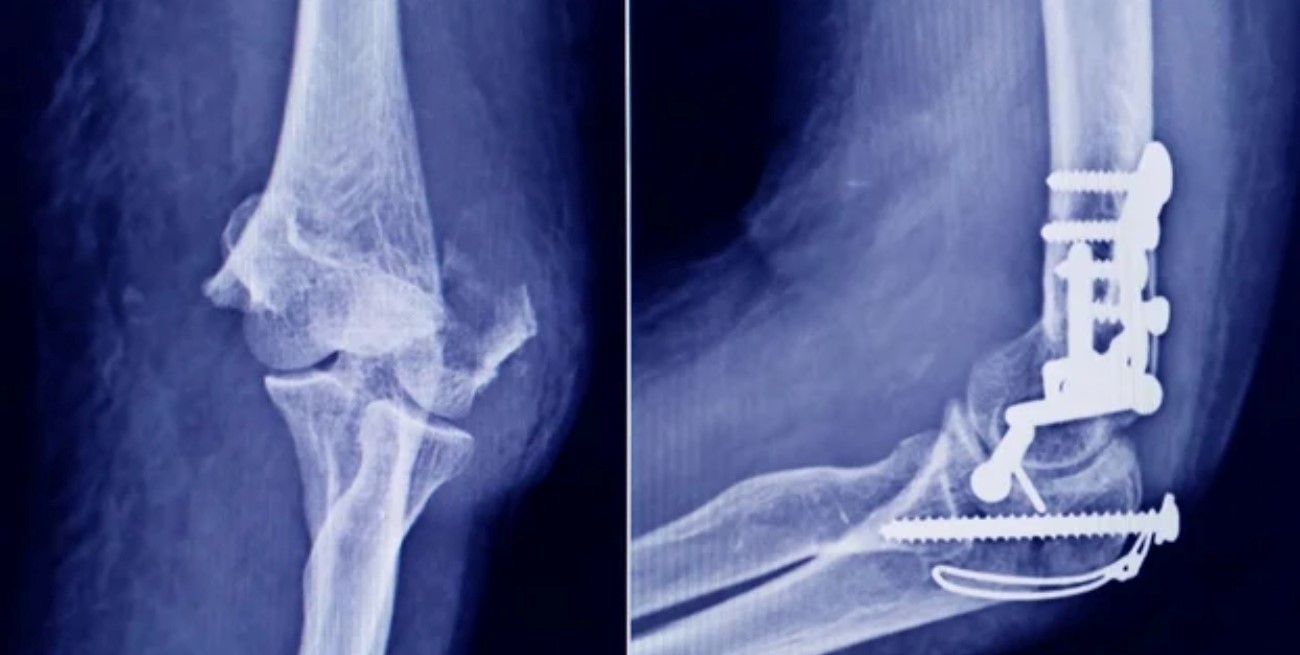

La Administración Nacional de Medicamentos, Alimentos y Tecnología Médica (ANMAT) emitió una alerta sanitaria para advertir a la población y a los profesionales de la salud sobre la detección de un tornillo falsificado utilizado en cirugías traumatológicas, cuyo uso podría implicar un serio riesgo para los pacientes.